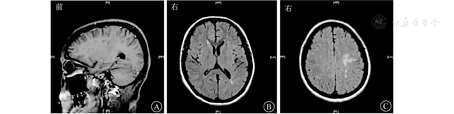

患者女,27岁,因"间断发热、头痛11个月,肢体麻木、纳差1 d"于2015年5月29日收治武汉市医疗救治中心。2014年5月患者因原发性不孕行体外受精-胚胎移植术,其后间断低热,8月下旬经超声检查提示死胎,即在外院行清宫术。9月下旬发热症状再次加重,在外院经抗感染治疗后一度好转。11月初患者再次出现发热,体温多在39 ℃左右,伴头痛、呕吐,经青霉素640万U,2次/d抗感染治疗后未见好转。反复在外院就诊,2014年11月9日行腰椎穿刺查脑脊液结果示白细胞计数55×106/L,乳酸脱氢酶35 U/L,总蛋白2 278 mg/L(表1);结核感染T淋巴细胞斑点试验阳性。11月10日行头颅MRI提示脑干、双侧小脑半球、双侧额叶及右侧颞叶异常强化灶(图1),诊断为结核性脑膜脑炎。彩色多普勒超声示子宫壁多发性钙化灶,子宫后壁囊性包块,考虑合并生殖系统结核。否认既往特殊病史。婚育史:患者20岁结婚,婚后7年内未避孕情况下未能正常受孕。予异烟肼0.4 g/d、利福平0.45 g/d、吡嗪酰胺1.25 g/d联合抗结核治疗后病情渐有好转,除吡嗪酰胺治疗5个月后停药外,其余药物持续应用于整个抗结核疗程中。2015年5月28日患者突发急性脑梗死,表现为吐词不清、左上肢乏力,遂入院治疗。6月2日复查头颅MRI见新发脑梗死病灶,但脑膜强化减轻(图2),6月5日查脑脊液相关指标好转(表1),加强抗结核治疗(异烟肼0.4 g/d、利福平0.6 g/d、吡嗪酰胺1.5 g/d、对氨基水杨酸钠8.0 g/d、阿米卡星0.6 g/d、左氧氟沙星0.6 g/d),辅以脱水、抗感染等治疗后好转出院。2015年7月19日患者突发运动性失语进行性加重,右侧肢体麻木,活动受限,伴有胸闷、气促,感疲乏无力,再次就诊,头颅MRI提示颅脑梗死病灶较前明显,但脑膜强化较前减轻(图3),2015年7月22日再次查脑脊液结果示总蛋白441.4 mg/L,白细胞计数、氯化物、葡萄糖等指标无异常(表1)。体格检查:神志清楚,反应稍迟钝;颈软,颈动脉搏动正常,双侧颈动脉未闻及血管杂音;双侧瞳孔等大等圆,对光反射灵敏,右眼外展不到边;伸舌右偏;右侧上肢肌力4+级,右下肢肌力4级,右侧Babinski征阳性,Kernig征阴性,右侧腱反射亢进,提示右侧肢体偏瘫。进一步行头颅磁共振血管成像(magnetic resonance angiography, MRA)示双侧大脑前、中动脉不显影、侧支循环增粗紊乱,Willis环特征性改变符合烟雾病(图4)。继续完善实验室检查,结核蛋白芯片检测38 000蛋白、脂阿拉伯甘露糖及结核分枝杆菌抗体-IgG均阳性,结核感染T淋巴细胞斑点试验阳性,抗核抗体谱2、抗中性粒细胞胞浆抗体、梅毒螺旋体抗体阴性;颈动脉彩色多普勒超声无异常;肿瘤标志物阴性;一次脑脊液抗酸染色阳性,因此排除其他感染、占位等因素,再次确认结核感染诊断,综合以上结果,诊断为结核性脑膜脑炎合并烟雾病。维持原方案抗结核治疗,并给予甘露醇稳定颅内压、地塞米松、吲哚布芬抗感染、营养神经、改善脑循环及防治血管性痴呆等治疗,患者脑梗死相关症状逐渐好转,肢体功能恢复,生活可以自理,而后出院继续服药治疗,治疗过程中定期复查腰椎穿刺脑脊液检查及头颅MRI检查等,抗结核治疗2年后复查头颅MRI提示脑膜强化等基本吸收(图5),抗结核治疗2年满疗程停药。